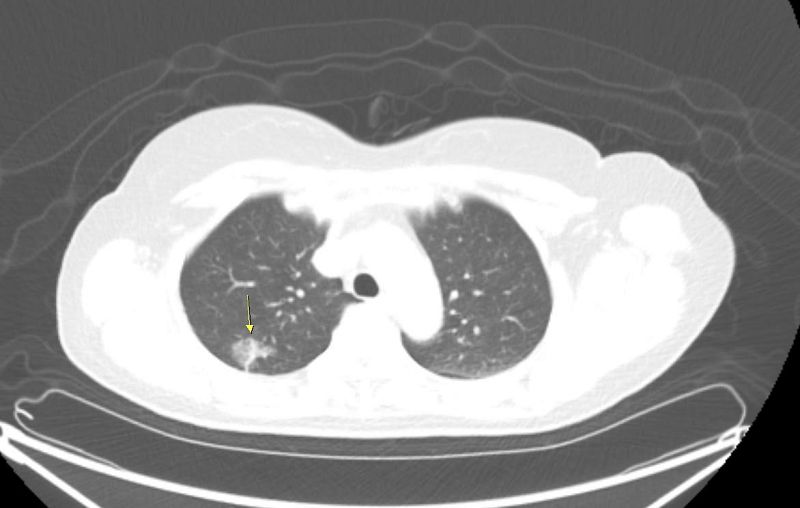

肺癌病人早期幾乎沒症狀,而腫瘤只要達1公分就可能轉移。若已出現咳嗽、咳血、喘、疼痛、體重減輕等症狀時,多已經到晚期。徐中平副院長指出,經低劑量電腦斷層檢查發現如毛玻璃霧面狀病灶,就需要定期追蹤。若超過0.8公分或質地較扎實,則病灶有可能已癌化。如情況許可手術切除為第一選擇,其他尚有放射線治療、化學治療、標靶治療、免疫治療等各種療法。其中標靶治療與免疫治療須先做基因檢測,有特定基因表現才適用,而健保對符合條件的病患也會給付。

徐中平副院長說,目前肺癌病例近七成是肺腺癌,共同點是沒有明顯症狀。有些病灶的電腦斷層影像看起來像是毛玻璃的黑影,這可能是癌前病變或原位癌;有些病灶則看起來較扎實,那就有可能是較具侵犯性的腫瘤。花蓮慈院10年前將LDCT納入同仁健檢項目,也因此有許多同仁發現早期肺癌即時手術治療,都有良好的治療結果。